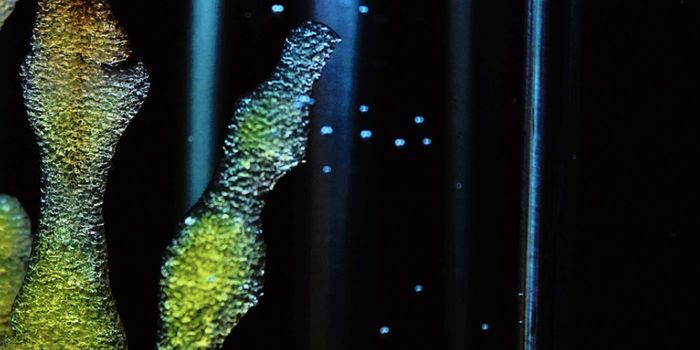

SEP 11, 2024Earth & The EnvironmentHow can oceanic microbes help produce antibiotics? This is what a recent study published in Nature Communications hopes ...